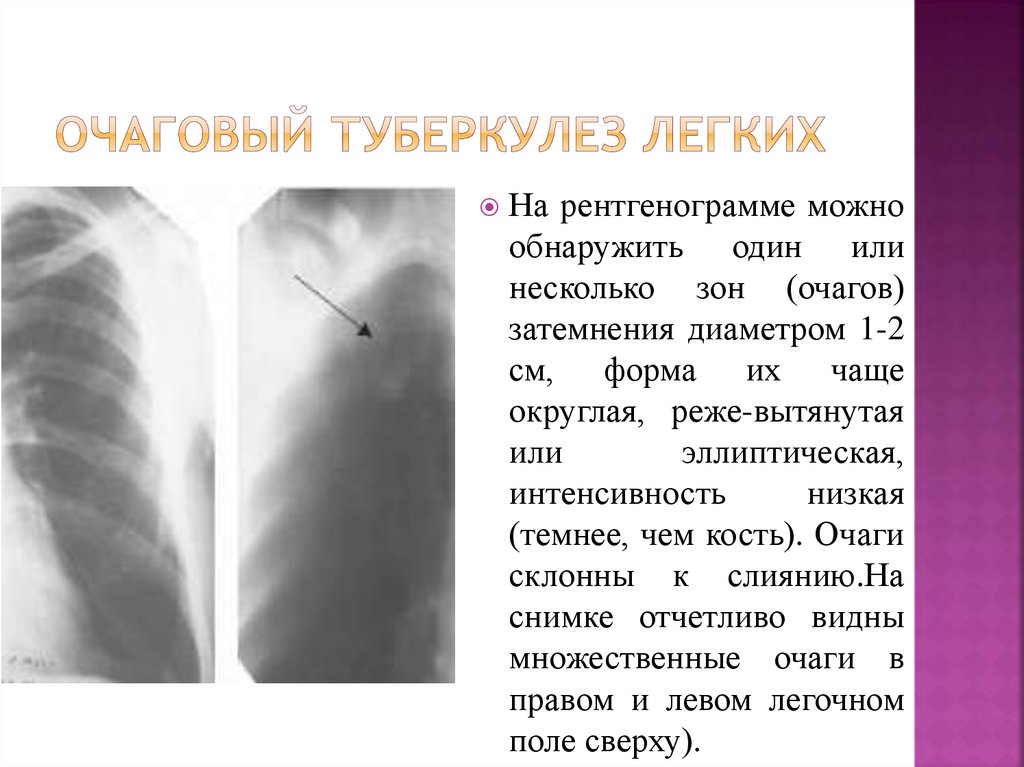

Очаговый и инфильтративный туберкулез презентация - 94 фото